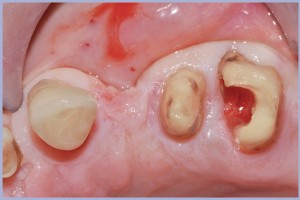

- Fig. 24 – Estrazione della radice

- Fig. 25 – Preparazione osteotomica flapless